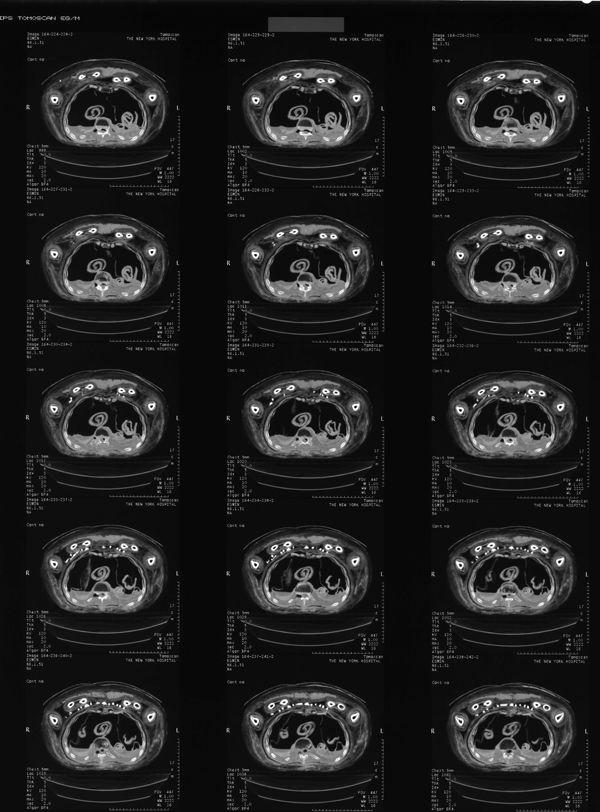

Fig. 8. CT scan of the chest area from 1997 that shows a section of the chest with the amulets.

Radiographic analysis can not only detect objects within the wrappings, but it can also provide information about mummification techniques or the health of an individual. In Nesmin's case we can, for example, see that most of his organs were removed, mummified separately, and then placed back into the chest and stomach cavity (see fig. 8); this was a common practice in the Ptolemaic Period. Images of his hips revealed that he suffered from arthritis.3

Older X-rays and CT scans of Nesmin that were taken in 1995 and 1997 (figs. 7–8, 10, and 13)2 had shown that his mummy is accompanied by a very large set of amulets (thirty-one in total) within the wrappings. The images that were produced at the time were on film and allowed the identification of the types of amulets (such as a standing god), but the information from these old images was limited and the visible details were not sufficient to permit the identification of the particular gods included, for example.